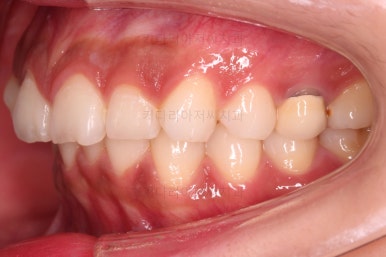

1. 초진

연산동교정치과 초진 시 입안의 모습입니다.

얼핏 앞에서 봤을 때 치열이 나쁘지 않아 보이는데요.

대신 자세히 살펴보면 윗니 양쪽 송곳니가 덧니처럼 볼록 튀어나와 있고요.

아랫니 어금니가 하나 없어서 주위 치아들이 해당 위치로 쓰러진 상태였습니다.

그리고 양쪽의 교합이 톱니바퀴처럼 맞물려 있는 것 같지만 톱니바퀴가 한 칸씩 밀려서 맞물려 있는 부정교합이 있는 상태였습니다.